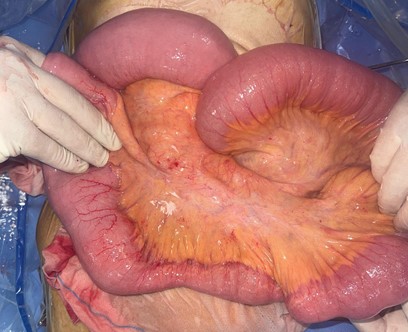

Midline laparotomy revealed a moderate serous peritoneal effusion, a small bowel volvulus with two counterclockwise turns, and a thickened, sub-stenotic segment approximately 10 cm in length, located 160 cm from the ligament of Treitz. The bowel was viable.

Figure 3: Intraoperative view showing the segmental sub-stenotic bowel wall thickening.

Detorsion of the small bowel followed by segmental resection of the thickened segment with hand-sewn end-to-end anastomosis was performed. Postoperative recovery was uneventful, and the patient was discharged on postoperative day four.

Histopathological analysis reveals chronic inflammatory remodeling without specific features and shows no evidence of malignancy.

The pathophysiology involves twisting of the mesenteric root, leading initially to venous obstruction followed by arterial compromise, which may progress to bowel necrosis if untreated. Primary volvulus is usually associated with anatomical predispositions, whereas secondary volvulus occurs in the presence of local pathological lesions such as postoperative adhesions, inflammatory strictures, tumors, or segmental bowel wall thickening [3,6]. In our case, the presence of sub-stenosing wall thickening suggested a secondary cause, requiring systematic histological analysis to rule out Crohn’s disease, intestinal tuberculosis, or neoplastic processes.